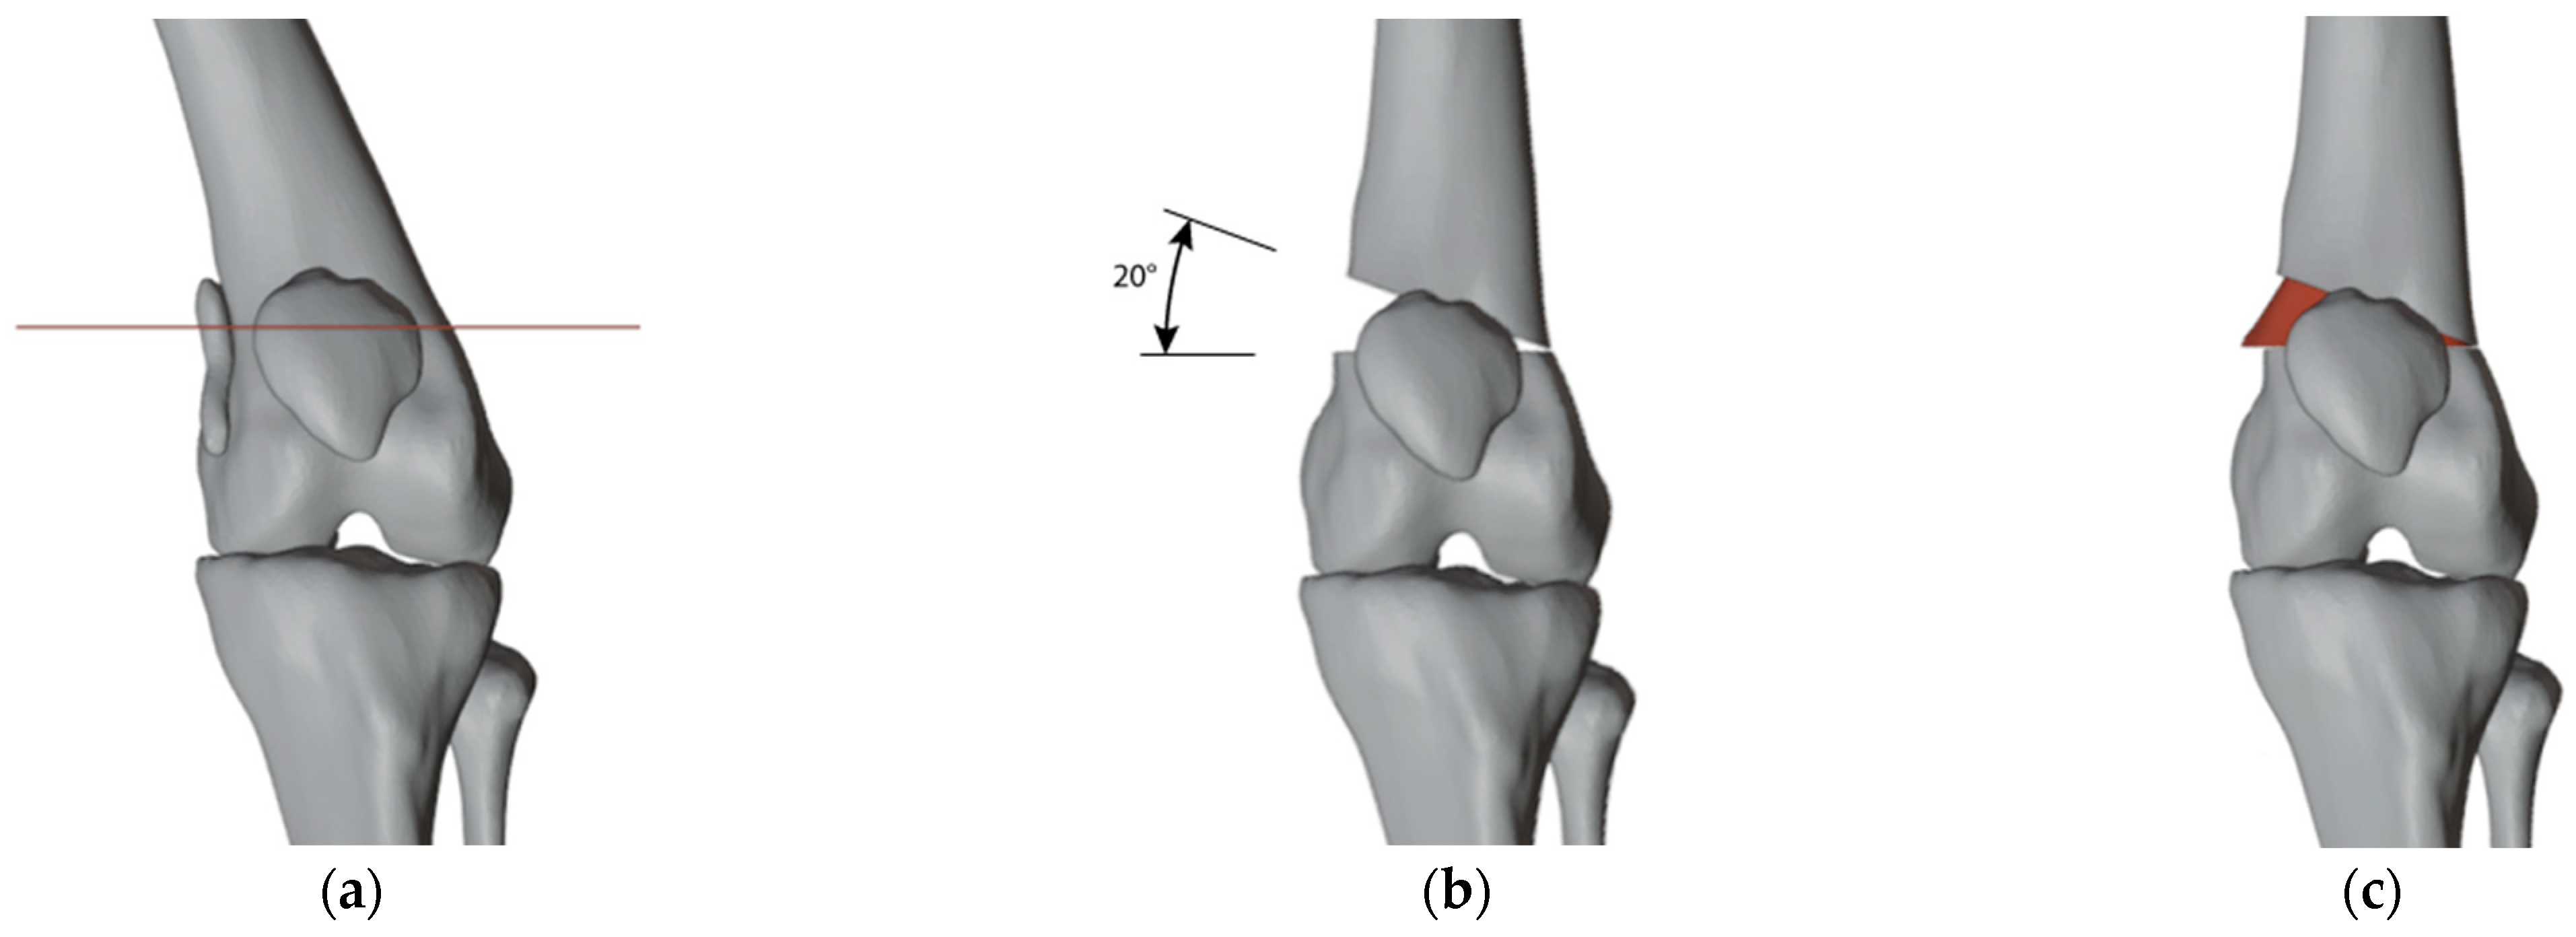

2.3. Surgical Simulation and Planning

2.4.1. PSIs Design for the Right Femur

2.4.2. PSI Design for the Left Femur